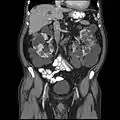

Autosomal dominant polycystic kidney disease

Other namesAutosomal dominant PKD, adult-onset PKD

Polycystic kidneys

Autosomal dominant polycystic kidney disease (ADPKD) is one of the most common, life-threatening inherited human disorders and the most common hereditary kidney disease.[1][2] It is associated with large interfamilial and intrafamilial variability, which can be explained to a large extent by its genetic heterogeneity and modifier genes.[1] It is also the most common of the inherited cystic kidney diseases — a group of disorders with related but distinct pathogenesis, characterized by the development of renal cysts and various extrarenal manifestations, which in case of ADPKD include cysts in other organs, such as the liver, seminal vesicles, pancreas, and arachnoid membrane, as well as other abnormalities, such as intracranial aneurysms and dolichoectasias, aortic root dilatation and aneurysms, mitral valve prolapse, and abdominal wall hernias.[1][3][4] Over 50% of patients with ADPKD eventually develop end stage kidney disease and require dialysis or kidney transplantation.[1][5] ADPKD is estimated to affect at least one in every 1000 individuals worldwide, making this disease the most common inherited kidney disorder with a diagnosed prevalence of 1:2000 and incidence of 1:3000-1:8000 in a global scale.[6][7][8][9][10]